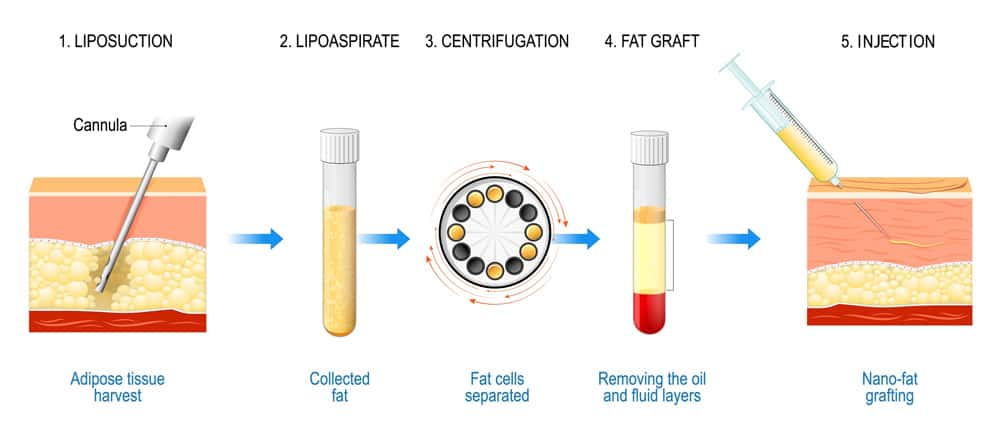

To extract & collect the fat, surgeons use liposuction with a blunt cannula in a 2-3mm cut created on your body. The cannula is moved back & forth to loosen the fat so it can be removed evenly. This movement looks really rough but usually doesn’t hurt. The area is injected with lidocaine/a numbing agent before this process occurs.

Regardless of the technique, at the end of the extraction you’ll be left with a syringe full of an orange substance. This is a mix of fat tissue, blood & oils.

1. Centrifugation

The mixture is spun in a centrifuge, which separates it into layers of blood that sits at the bottom, fat that sits in the middle, and oil that rises to the top. The blood & oil layer is removed, and the fat might be spun again to make sure no blood or oils are left.

To extract & collect the fat, surgeons use liposuction with a blunt cannula in a 2-3mm cut created on your body. The cannula is moved back & forth to loosen the fat so it can be removed evenly. This movement looks really rough but usually doesn’t hurt. The area is injected with lidocaine/a numbing agent before this process occurs.

Regardless of the technique, at the end of the extraction you’ll be left with a syringe full of an orange substance. This is a mix of fat tissue, blood & oils.

1. Centrifugation

The mixture is spun in a centrifuge, which separates it into layers of blood that sits at the bottom, fat that sits in the middle, and oil that rises to the top. The blood & oil layer is removed, and the fat might be spun again to make sure no blood or oils are left.